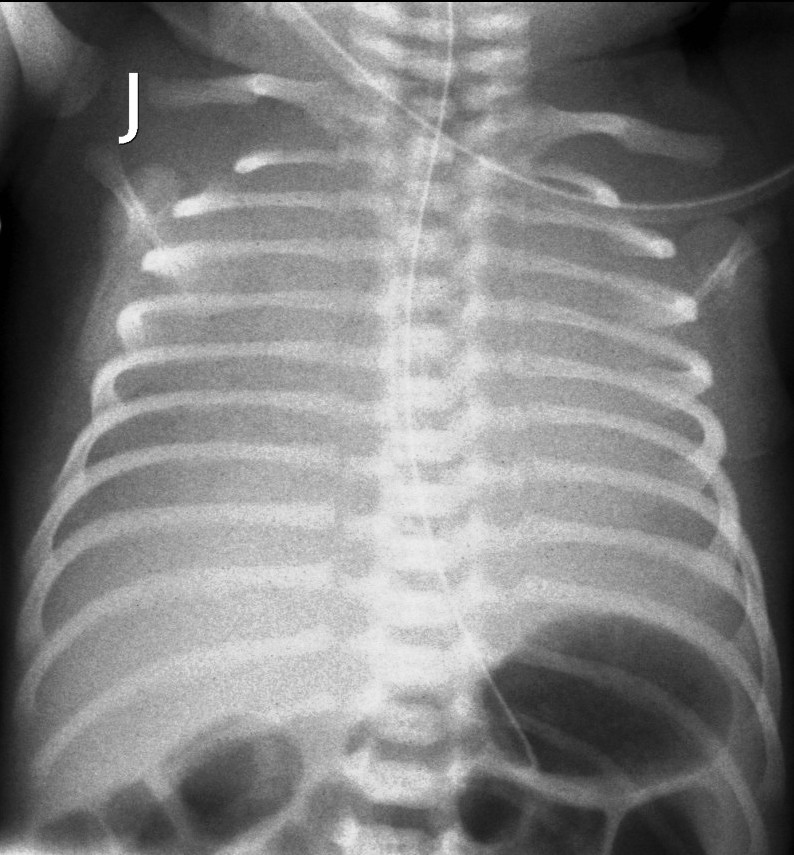

IRDS (Idiopathic respiratory distress syndrome). Preterm infants, younger than 34 weeks, have immature lungs with surfactant shortage that leads to alveolar insufficiency. The breathing disorder progresses with time as tachypnea, dyspnea, cyanosis and grunting occur. On X-ray images the respiratory volume will regress and a diffuse reticular-nodular pattern can be observed, also wide air-bronchograms will appear running to the peripheries. The contours of the heart will be blurred or even a complete loss of transparency is visible (stages I-IV). Surfactant administered in time will result in improved radiologic picture.

Image

3.“White” lung. IRDS.IV.